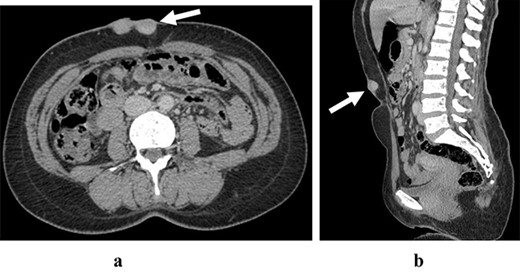

The abdominal CT scan in axial section (a) and sagittal section (b) are showing an heterogeneous enhanced lesion of the anterior abdominal wall respecting aponeurotic facia

A 45-year-old woman complained of the occurrence of a small cutaneous lesion on the AAW evolving over the past precedent 3 years. The swelling volume had progressively increased. The physical examination revealed an oval mass with regular borders and a polylobed surface; the lesion was localized at the supra-umbilical level of AAW, and slightly lateralized on the right with dimensions of 5 cm by 3 cm (Fig. 1). The palpation revealed a hard and fixed swelling on the skin. However, it remains freely mobile regarding the deeply musculoaponeurotic plane. The histopathological findings on the skin biopsy were consistent with DFSP. The thoracic–abdominopelvic computed tomography (CT) scan did not show any metastatic lesions. The abdominal CT sections showed a well-defined enhancing soft tissue density lobulated lesion measuring 5.8 × 1.5 cm and arising from the AAW. The lesion presented a discreetly heterogeneous enhancement. It infiltrated subcutaneous tissue without any involvement of the musculoaponeurotic plane which remained distant from the lesion (Fig. 2). The patient underwent WLE with minimal macroscopic safety margins of 3 cm from the visible and palpable limits of the tumor (Fig. 3). The resulting defect was repaired with primary closure by advancing the adjacent tissue. Indeed, the cutaneous and subcutaneous tissue under the wound caudal edge was raised off anterior abdominal aponeurosis which facilitated flapping advancement and wound-free-tension coverage (Fig. 4a). We obtained an acceptable esthetic result in the form of a transverse mid-abdominal scar (Fig. 4b). The recovery was simple. The specimen histopathology revealed a characteristic of DFSP appearance with spindle cells in a storiform arrangement (Figs 5 and 6). The immunohistochemistry confirmed the diagnosis by revealing cluster differentiation 34 (CD 34) expression (Fig. 7). The margins are microscopically safe. The final decision of the multidisciplinary meeting consisted of surveillance. After 4 years of follow-up, no locoregional or distant recurrence was observed.

The tumor staging depends on the size and the tumor history. Indeed, in the case of small and superficial DFSP, the tumor extent and mobility, as well as a regional node can be easily assessed by physical examination [5]. Nevertheless, in routine clinical work, the imaging tools such as ultrasound and CT scan are often used and allowing to confirm the extension and provide objective lesion documentation for the surgical planning. CT reveals a solitary, subcutaneous lobular–nodular architecture and soft tissue attenuation and post-contrast agent enhancement. Besides, a CT scan is useful to evaluate distant metastatic patterns [6]. However, in the case of a large tumor or recurrent primary tumor, magnetic resonance imaging (MRI) is crucial in delineating the size and extent of the tumor, as well as its connection to adjacent neuromuscular and bone structures. [5].